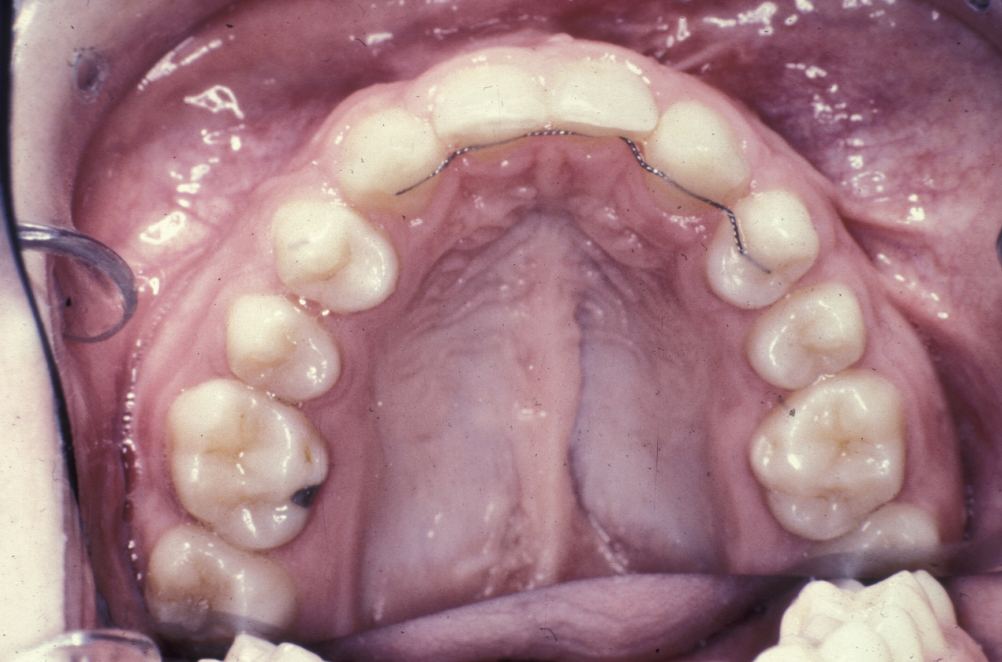

Collaboration with the orthodontist on this is essential, both in terms of timing of the bone graft and in terms of arch expansion and stabilisation of the maxilla. Particularly in cases of bilateral alveolar bone grafting, the premaxilla should be stabilised with a heavy arch wire and either a tri- or quad-helix (a heavy wire orthodontic appliance). This provides optimum stability for the grafted bone. Preoperative removal of deciduous teeth and visible supernumerary teeth six weeks prior to alveolar bone grafting creates healthy attached gingivae and optimises the flap design.

Figure 7: The long-term result; surgery without orthodontics is a waste of time. Here the teeth have been aligned after palate and alveolus repair.